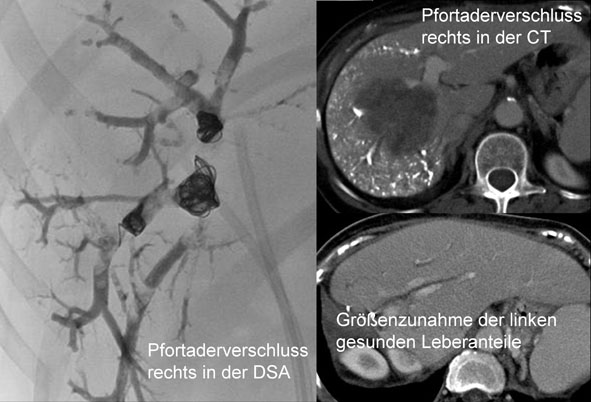

• Chemoembolisationen

• Organinterventionen inkl.

• TIPS (transjugulärer portosystemischer (Leber)-Shunt